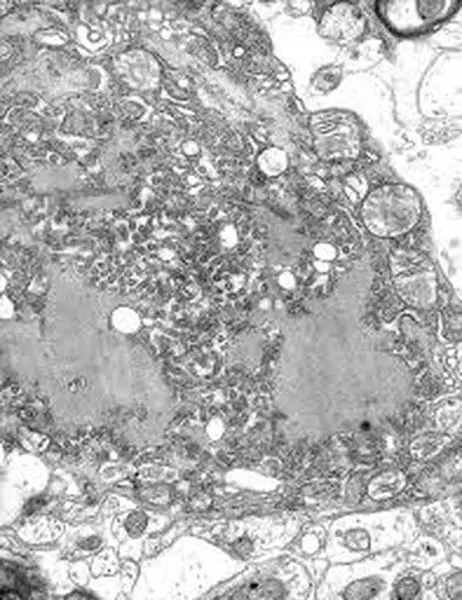

瘋狗症病毒(網上圖片)